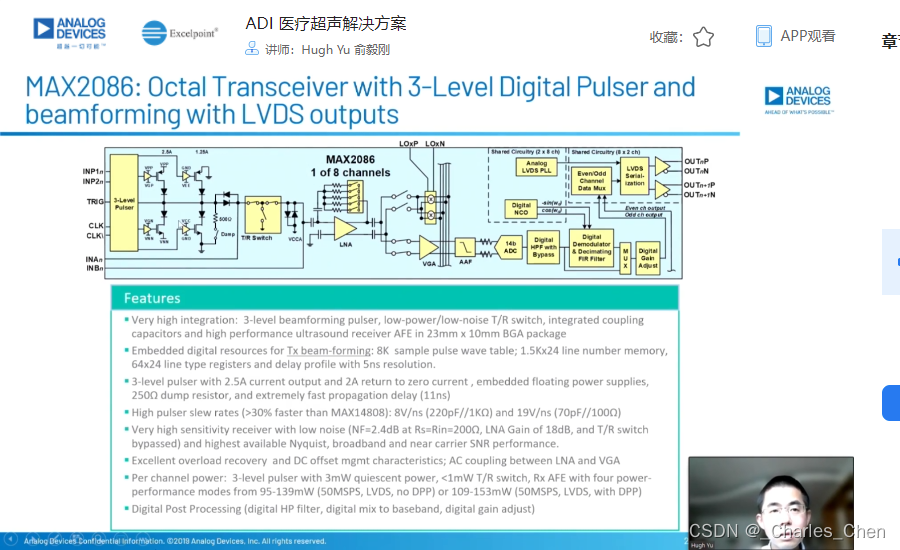

数字发射波束成形器用于产生所要求的数字发射信号,以正确的时间和相位生成聚焦发射信号。高性能超声系统可通过任意波形发生器产生复杂的发射波形,从而优化图像质量。这些情况下,发射波束成形器以大约40MHz速率生成8位至10位数字字符,并以此产生所要求的发射波形。数/模转换器(DAC)将数字波形转换成模拟信号,通过线性高压放大器进行放大,用于驱动传感器单元。由于这种发射技术占用较大体积,而且价格昂贵、需要消耗较高能量,所以,这种架构只限于昂贵的非便携设备。多数超声系统并不使用这种发射波束成形技术,而是采用多级高压脉冲发生器产生需要发射的信号。在这种替代方案中,利用高集成度、高压脉冲发生器快速切换传感器单元至适当的可编程高压电源,产生发射波形。为了产生一个简单的两极发射波形,脉冲发生器需要交替地将传感器单元切换到由数字波束成形器控制的正、负发射电压。更复杂的设计可以让传感器单元切换至多路电源和地,从而产生更复杂、性能更好的多重波形。

近几年,随着二次谐波成像的广泛应用,高压脉冲发生器对于斜率和对称性的要求越来越高。二次谐波成像利用了人体的非线性声学特性。这些非线性特性倾向于将频率fo的声能转变成2fo频率。多种原因使得接收二次谐波信号能够获得更高的图像质量,因此,二次谐波成像得到了广泛应用。

二次谐波成像有两种基本的实现方法。一种称为标准谐波成像,尽可能抑制发射信号的二次谐波,从而使接收到的二次谐波主要源于人体的非线性。这种模式要求二次谐波的发射能量至少低于基波能量50dB。所以,发射脉冲的占空比要求是准确的50%且误差小于±0.2%。另一种方法称为脉冲反相,利用反相后的发射脉冲产生同一图像路径的相位相反的两路接收信号。在接收器中对这两路反相接收信号求和,恢复由于人体非线性产生的谐波信号。这种脉冲反相的方法必须在叠加时尽可能抵消发射脉冲的反相成分。所以,高压脉冲发生器的上升时间和下降时间必须严格一致。

成像通道接收机

超声成像通道的接收机用于检测二维(2D)信号以及彩超流体成像所需的脉冲多普勒(PWD)信号和频谱PWD。接收机包括Tx/Rx开关、低噪声放大器(LNA)、可变增益放大器(VGA)、抗混叠滤波器(AAF)和模/数转换器(ADC)。